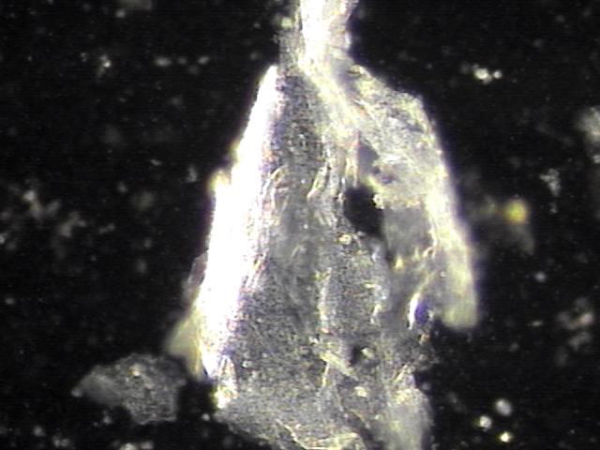

주3회 치료중 정관과 사정관,전립선내 그리고 정낭등에 막혀 있던 섬유소 덩어리가 치료된 현미경학적 사진입니다.

This is a microscopic image showing fibrin clumps that had been blocking the vas deferens, ejaculatory ducts, prostate, and seminal vesicles, which were resolved during the course of targeted treatment three times a week.